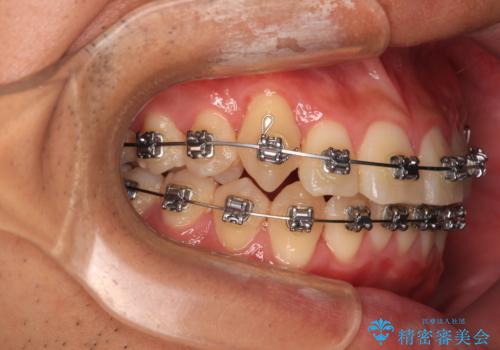

- メタルブラケット

マウスピース矯正とワイヤー矯正で悩んでいらっしゃいましたが、非常に強い咬合力であることや、お仕事柄不規則な生活リズムになることが多いとのことで、ワイヤー装置にて矯正治療を行うこととしました。

口元が突出する仕上がりとならないように、舌突出癖改善のトレーニングをしっかりと行っていただきながら、矯正治療を進めていくこととしました。